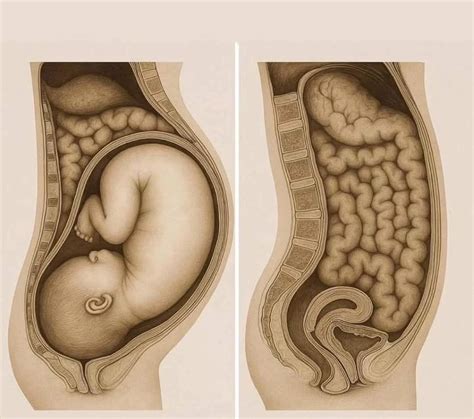

Piaty mesiac je obdobím dynamického rastu a vývoja vášho dieťatka. Z veľkosti prirovnateľnej k mangu na začiatku mesiaca, sa na jeho konci zmení na približnú veľkosť kokosového orecha.

Kľúčové Míľniky Vývoja Plodu:

- Odtlačky Prstov: Na bruškách prstov sa tvoria papilárne línie, ktoré zabezpečia jedinečnosť odtlačkov prstov každého človeka.

- Vývoj Mozgu: Začína sa formovať mozgová kôra, ktorá je zodpovedná za zložité myšlienkové procesy.

- Vernix Caseosa (Mázok): Tvorí sa vernix, biela mazová hmota pokrývajúca pokožku plodu. Táto ochranná vrstva chráni dieťatko pred dlhodobým pôsobením plodovej vody a uľahčuje pôrod.

- Funkcia Orgánov: Pomaličky svoju funkciu začína vykonávať pečeň.

- Očné Dúhovky: Očné dúhovky sa sfarbujú namodro. Konečná farba očí sa však ustáli až v prvom roku života dieťaťa.